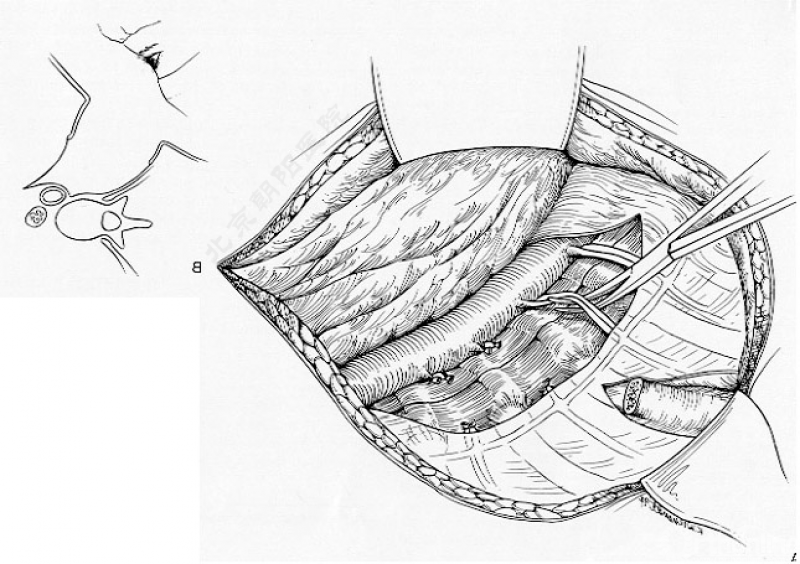

切开纤维环,去除终板椎间盘组织,直至纤维环的后侧边缘,对于严重侧凸如果需要可至后纵韧带。

进一步使用刮匙和髓核钳完整去除椎间盘组织和终板,营造植骨面。

内固定选择的是5.5mm双棒系统,先置入顶椎的螺钉垫板。

置入顶椎的椎体螺钉,螺钉可置入椎体中部到后方1/3之间的范围内。

使用双棒系统时,先置入背侧的螺钉,螺钉指向椎体中线,后置入腹侧的螺钉,螺钉轻度指向后侧。形成对椎体的三角形抓持力。

胸腔侧、腹腔侧螺钉全部置入后,骨移植物植人的越靠近后纵韧带或者纤维环的后缘越好。

将预先折弯的金属棒先置入背侧。

椎间融合器经前方置入凹侧,确保腰椎前凸的恢复和冠状面畸形的矫正,将剩下的骨移植物置入椎间隙内。

置入腹侧金属棒。

使用双棒系统时先安装背侧的棒,可进行90°的去旋转,也可以直接通过前方螺钉矫正冠状面和矢状面的畸形,然后固定后方的棒,可进一步通过加压矫正冠状面畸形。